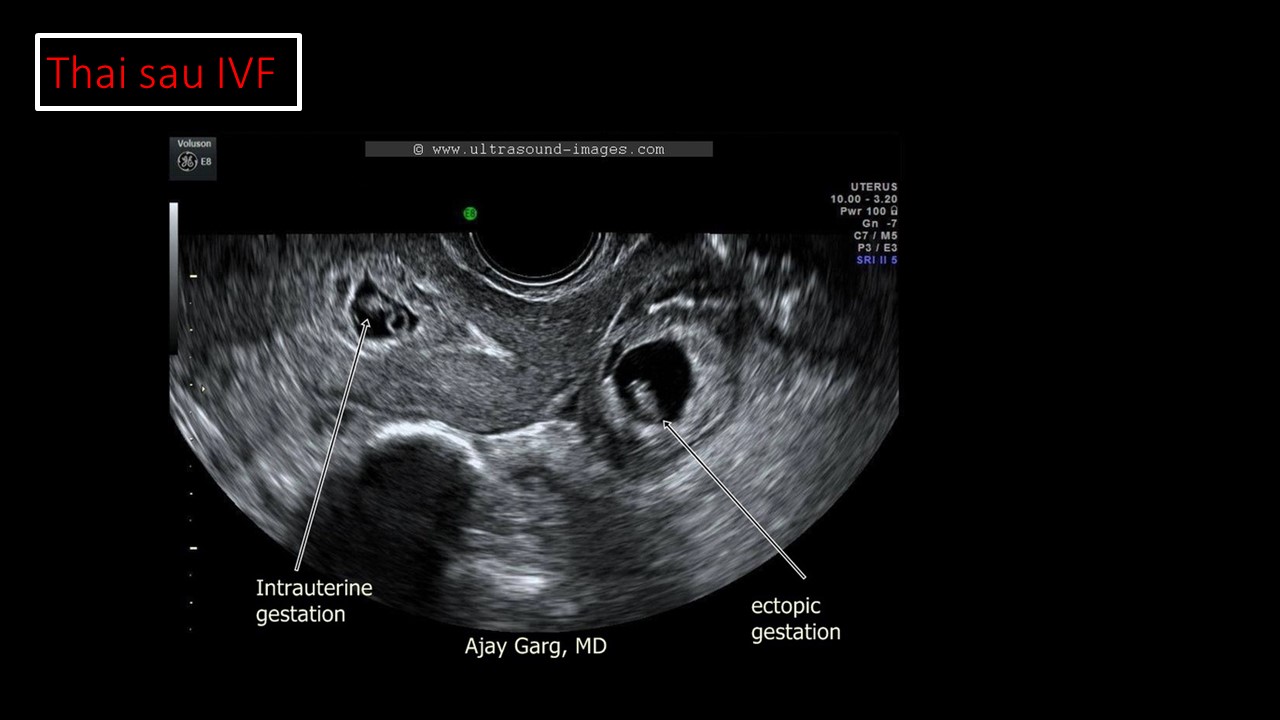

Vai trò của siêu âm trong chẩn đoán và điều trị hiếm muộn

Từ khóa: Vai trò của siêu âm trong chẩn đoán và điều trị hiếm muộn